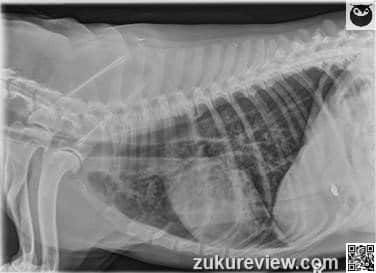

A 12-year-old female spayed Labrador retriever dog presents for dental cleaning.

After induction and intubation, her breathing became labored and her pulse oximetry decreased to 88%.

Thoracic radiographs are shown below.

What clinically significant finding on these radiographs explains the dog’s hypoxia?